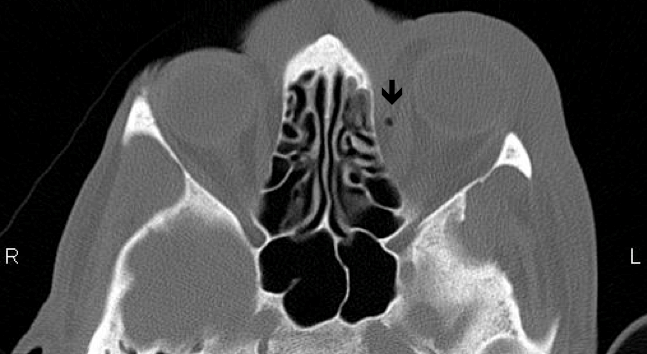

The following day, the patient re-presented with worsening orbital swelling now involving the left cheek. On further questioning, it was noted that he had a history of sinusitis and had recently suffered from an episode of upper respiratory tract infection. Ocular findings remained unchanged. Computed tomography (CT) scan revealed left orbit soft tissue swelling outside the globe along with soft tissue changes consistent with inflammation and a locule of air in the orbital cavity, medial to the medial rectus (Figure 2 [Fig. 2], Figure 3 [Fig. 3]). There were no signs of sinus infection or periosteal inflammation (Figure 2 [Fig. 2], Figure 3 [Fig. 3]). C-reactive protein (CRP) was raised at 35. A diagnosis of left orbital and facial cellulitis was made. The patient was admitted and commenced on 2 g of intravenous ceftriaxone once a day and 400 mg of metronidazole three times a day. Blood cultures did not show any organisms. The celluitis responded well to treatment and he was discharged two days later with oral antibiotics. Two weeks later, the patient was reviewed in clinic. His best, corrected visual acuity was 6/12 OD and 6/9 OS.

Figure 2: Coronal section of MRI scan showing air locule

Figure 3: Transverse section of MRI scan showing air locule